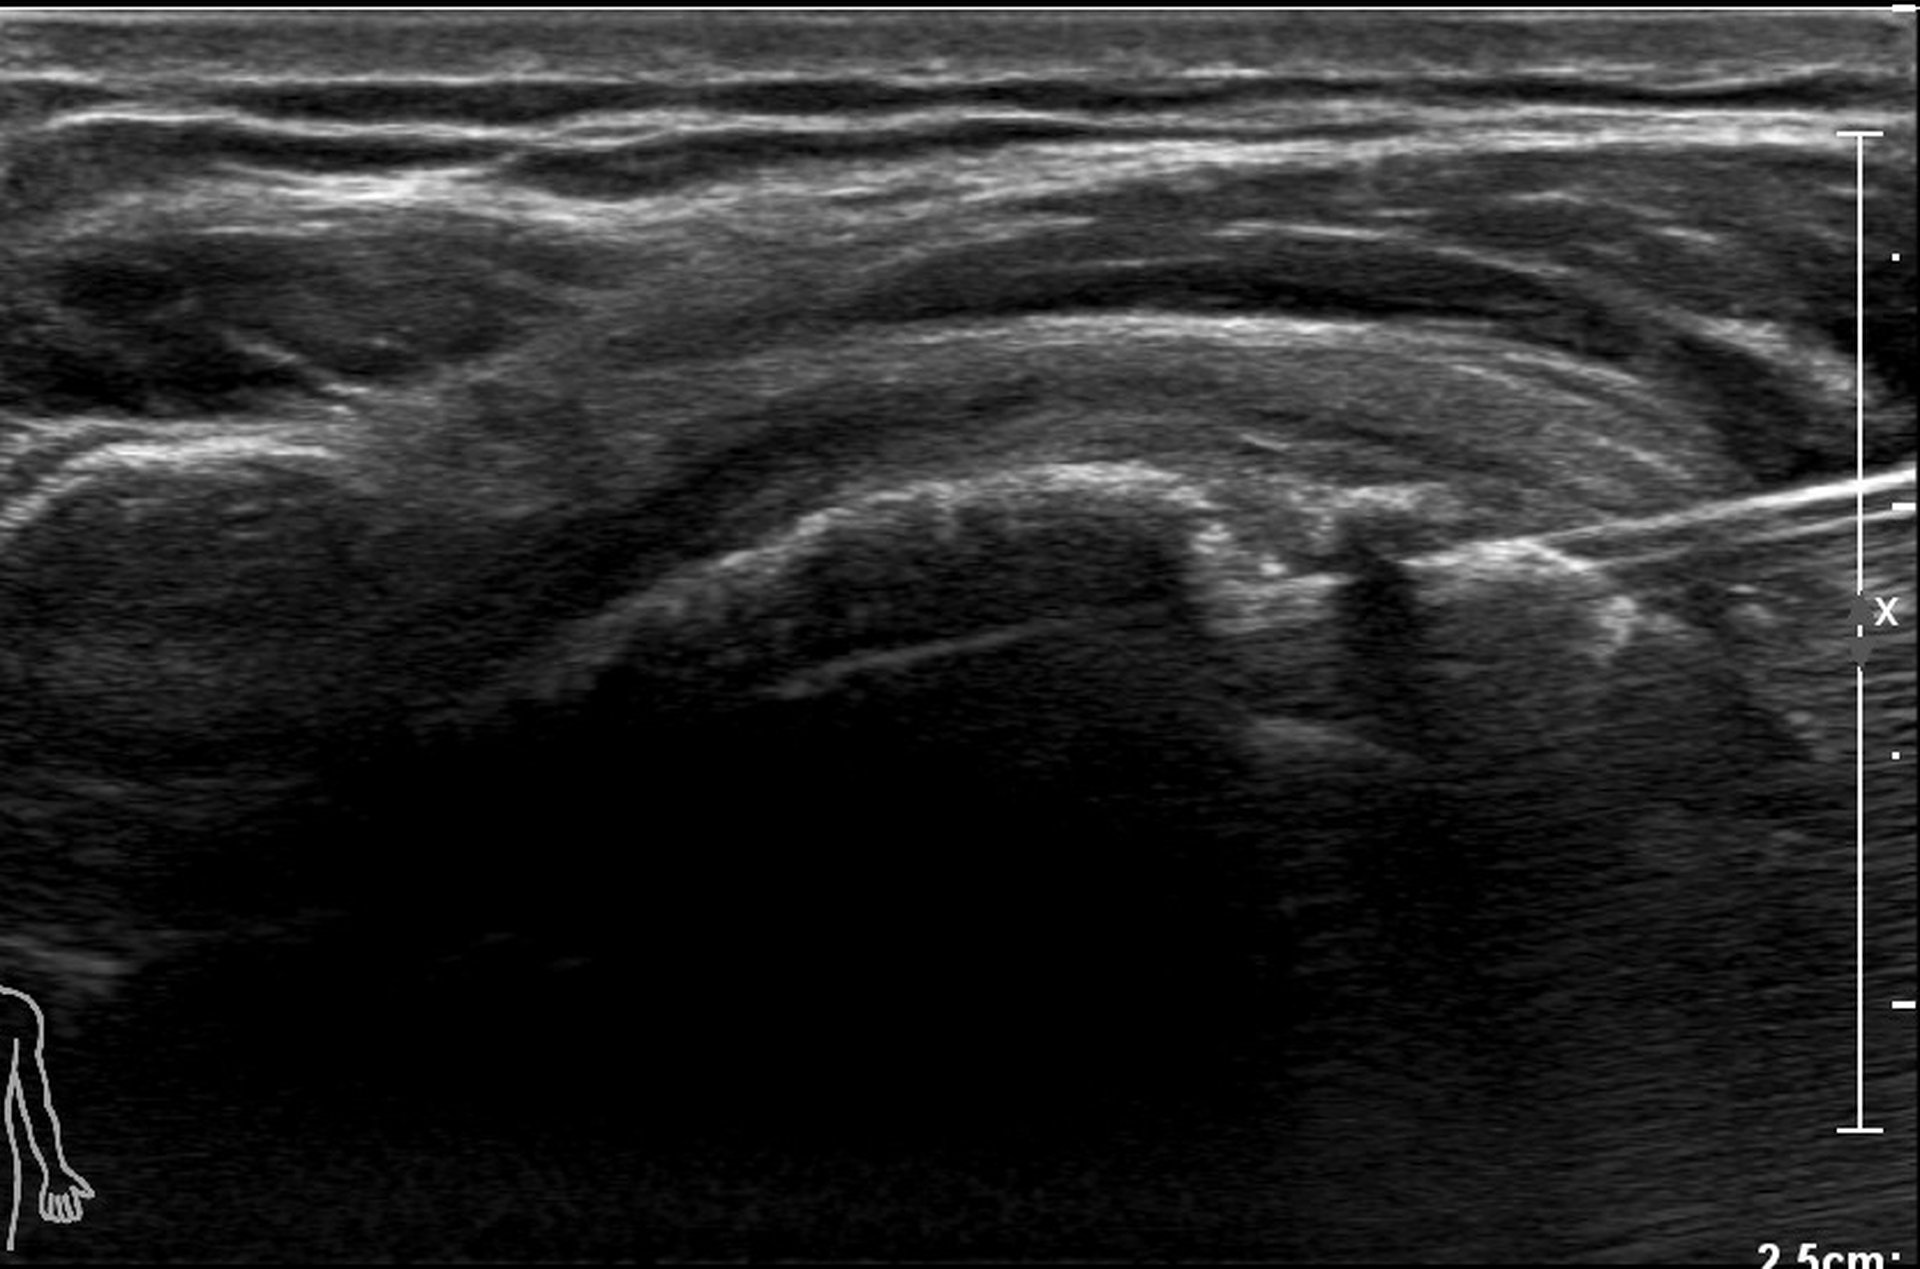

La ponction lavage de calcification tendineuse ou trituration est une technique de radiologie qui permet de faire régresser de volumineuses calcifications qui se sont formées au sein des tendons (de l’épaule le plus souvent) et sont responsable de douleurs.

Elle est réalisée sous contrôle échographique.

Il introduit ensuite une aiguille jusqu’à la calcification et procède à une ponction et lavage de celle‑ci, c’est‑à‑dire plusieurs passages et aspirations à l’aiguille fine au sein de la calcification afin de la ramollir. En fin de procédure, il injecte un corticoïde afin de limiter les douleurs secondaires.